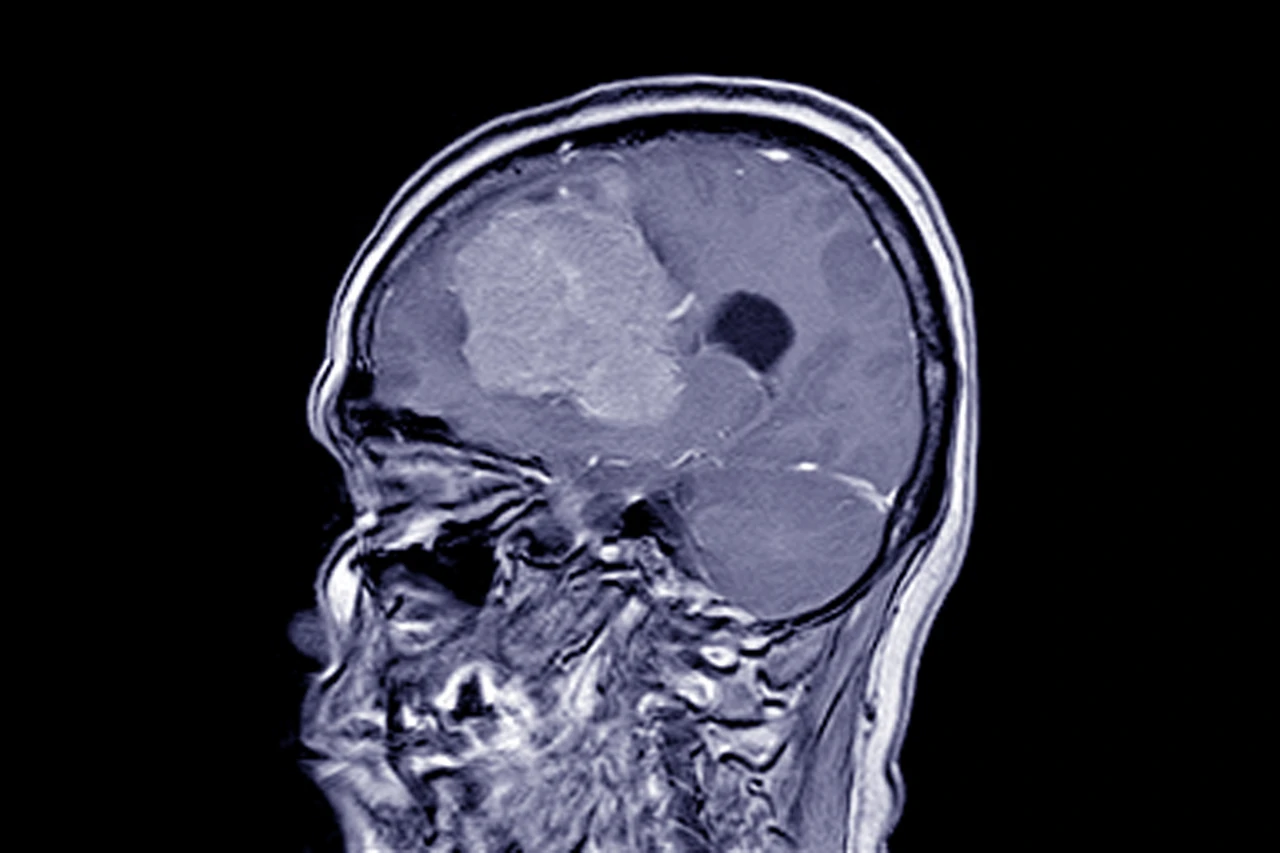

Менінгіома — це одна з найпоширеніших пухлин головного мозку, яка утворюється з оболонок, що його покривають. Хоча більшість таких утворень є доброякісними, питання, чи можливе повторне зростання менінгіоми після її видалення, хвилює багатьох пацієнтів. Адже навіть після успішної операції ризик рецидиву існує, і він залежить від багатьох факторів. Більше про те, які можуть бути наслідки операцій, можна дізнатися на сторінці — https://time.org.ua/naslidky-pislya-vydalennya-meningiomy/.

При появі подібних симптомів потрібно негайно звернутися до лікаря та пройти магнітно-резонансну томографію.

Методи виявлення повторного росту пухлини

Сучасна медицина дозволяє виявити навіть незначні зміни після операції. Для контролю стану пацієнта використовують:

• МРТ головного мозку — основний метод спостереження;

• КТ із контрастом, якщо потрібна додаткова точність;

Зазвичай МРТ рекомендують робити через 3–6 місяців після операції, а потім щорічно. Якщо ризик рецидиву високий, контроль проводять частіше.